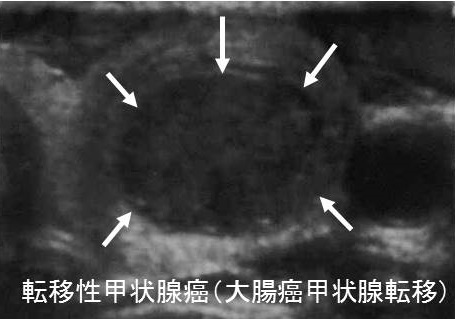

- 大腸がん:比較的稀。境界明瞭な低エコー領域であったとの報告あり。

エコー上、腺腫様甲状腺腫、良性濾胞腺腫、悪性の甲状腺濾胞癌と見分けが付きません。

ほとんどが、大腸がん肺転移も合併します。

(Int J Surg Case Rep. 2021 Apr;81:105804.)[甲状腺転移,肺転移にて発見された上行結腸癌の1切除例日臨外会誌71(3),766―770,2010]

転移性甲状腺癌の超音波検査(エコー)所見は、

- 低エコー輝度、あるいは低エコー領域

結節型、びまん型いずれもあり(Surg Today. 2014 Jan;44(1):55-61.)

- 結節型は腺腫様甲状腺腫、良性濾胞腺腫(淡明細胞型)、甲状腺濾胞癌と見分けが付きにくい